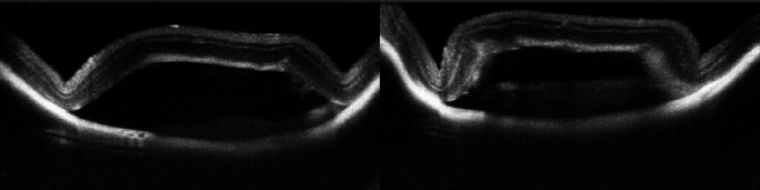

视网膜下腔注射-基因治疗、干细胞治疗

可视化视网膜下腔注射隆起高度定量化,对应药物剂量对视网膜影响研究

基因治疗、干细胞治疗视网膜下腔注射---排除视网膜下腔物理损伤得影响